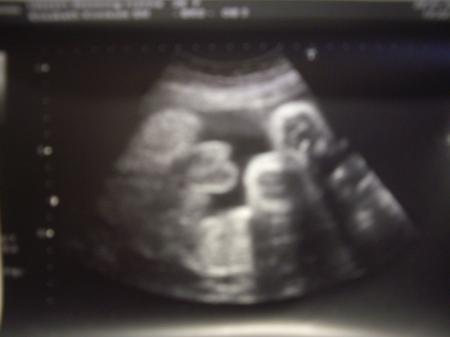

Hallo War heute zur Feindiagnostik,alles super So wie es sein soll. Nun kommt es aber zum Geschlecht des Babys. 3 mal wurde ein Mädchen festgestellt,hab auch schon was gekauft in rosa etc ,3 aussagen schienen mir glaubhaft genug. ;-). So nun guckt euch bitte das Bild an und sagt mir was ihr da seht .........

Bild zu Feindiagnostik Outing :-) OMG - Schwanger - wer noch? Rund um die Schwangerschaft

Warte noch etwas ab! Vielleicht ist dein baby gerade in einer Phase, wo "kleine" Sachen gerade recht groß erscheinen? Was ich sagen will: vielleicht ist es ein Mädchen, warte noch, bis man wirklich Umrisse von Hoden und Penis oder halt schamlippen erkennt. Das was ich da sehe könnte aus dem seltsamen Blickwinkel alles sein.

Na,wer so eindeutig zeigt,was er hat,der darf auch blaue Sachen tragen *lol*... Mein Großer zeigte es so kurz vor der Geburt (gewusst haben wir es schon in der 12.SSW):

Würde einen Jungen auch kein Rosa anziehen. Außer vielleicht Boddys oder im Garten das UV Schutz T-shirt. Und Glückwunsch zu Sohne Mann.